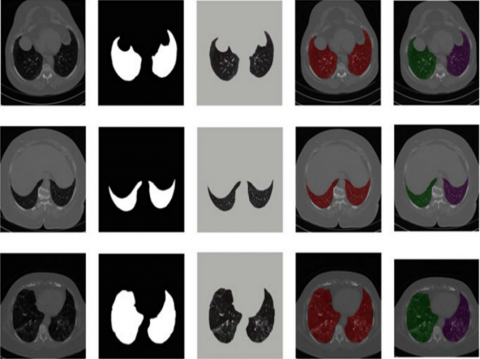

Pre-processing: The automatic lung segmentation approach is seen in Figure 5. In this stage, four critical processes are carried out: trachea and bronchus removal; optimum thresholding; connected component labelling; as well as separation of the left and right lungs. The procedure is detailed in the next section.

Figure 5. The block diagram of the proposed model

The lung parenchyma, trachea, and bronchial tree are all visible on the first CT scan of the lung. Fat, muscle, and bones may be seen on the exterior of the lung's anatomy. There are also nodules on the exterior of the lungs, which are called pulmonary nodules. In order to remove non-parenchymal tissues from a CT image, lung field segmentation must be performed. It is divided into many phases, which are as follows: The trachea and bronchi are removed by the use of a method known as region-growing. This is accomplished when the lung parenchyma has been separated from the surrounding architecture. After the left and right lungs have been put together, there are still certain pieces that need to be removed from the body.

Figure 6. The flow of the proposed architecture on the LuNa-16 dataset

When separating low density regions such as the lungs and airways from high density areas such as the chest, bones, fat, muscles, and pulmonary nodules (which have a high density of their own), the term "optimal thresholding" is used (non-body voxels). This technique is referred to as "optimal thresholding" (body-voxels). As seen in Figure 6, lung CT imaging reveals zones of low and high density. Instead of using a fixed threshold value, we employed optimal thresholding, which automatically determines the appropriate threshold for segmenting the data. This method significantly simplifies the task of accounting for minor variations in tissue density that may exist across different individuals. In order to determine the appropriate threshold, iterative approaches are used. To get things going, we employed repeated thresholding. If it was assumed that they were unsure of where to position the body voxels, this would be incorrect. There are no voxels that are not part of the body in this image. All of the other voxels in the image are part of the body. When the final run is completed, it displays the precise position of body and non-body voxels. Suppose that the threshold value is T at step t, which is what we'll state in the next paragraph. Initially, this threshold was utilised to distinguish between non-body and body voxels in the scene was shown in the Figure 7.

Figure 7. The proposed architecture for segmentation of bio-medical images